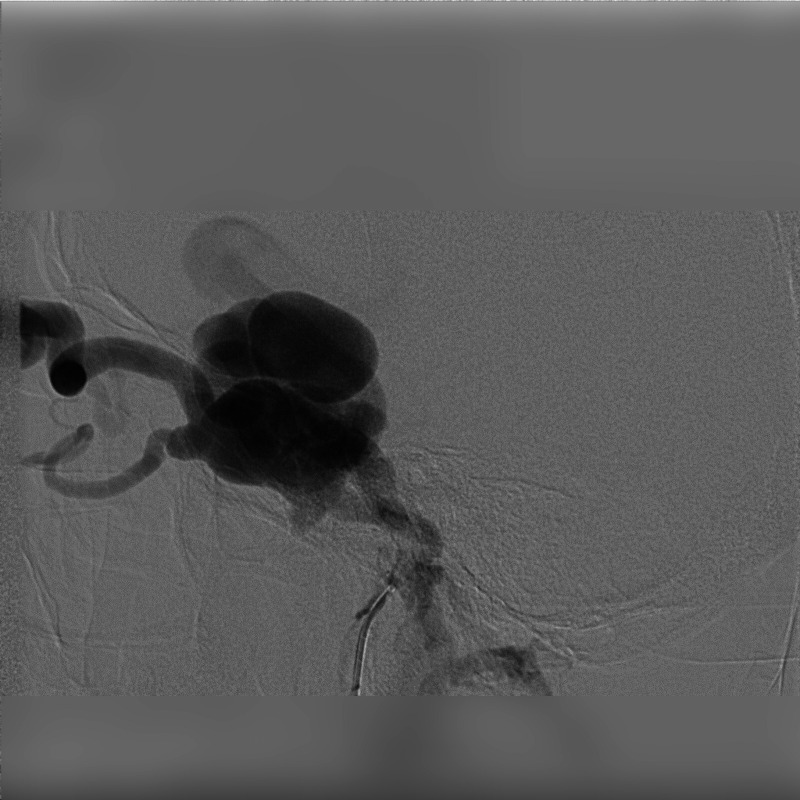

颈海绵状瘘(CCFs)是颈动脉和海绵窦之间异常的动静脉连接,由外伤引起。本病例报告提出一位47岁男性,在道路交通事故后发展为CCF。患者表现出搏动性眼球突出和眼球杂色等症状,这是CCFs的特征。通过数字减影血管造影(DSA)确认诊断,显示瘘的来源。患者采用显微手术和血管内介入治疗的新方法,包括内颈动脉结扎和经动脉线圈栓塞。治疗后症状迅速缓解,包括搏动性眼球突出和眼压。本病例强调了多学科方法的重要性,结合显微外科和先进的血管内技术,有效地治疗创伤性CCFs。该研究强调了早期诊断的价值和微创手术在改善患者预后方面的作用。

Carotid-Cavernous Fistulas (CCFs) are abnormal arteriovenous connections between the carotid artery and the cavernous sinus, resulting from trauma. This case report presents a 47-year-old male who developed a CCF following a road traffic accident. The patient exhibited symptoms such as pulsatile exophthalmos and an ocular bruit, characteristic of CCFs. Diagnosis was confirmed through Digital Subtraction Angiography (DSA), revealed the origin of the fistula. The patient was treated using a novel combined approach of microsurgery and endovascular intervention, involving ligation of the internal carotid artery and transarterial coil embolization. The treatment resulted in rapid resolution of symptoms, including the pulsatile exophthalmos and ocular bruit. This case highlights the importance of a multidisciplinary approach, blending microsurgical and advanced endovascular techniques, in effectively managing traumatic CCFs. The study underscores the value of early diagnosis and the evolving role of minimally invasive procedures in improving patient outcomes.